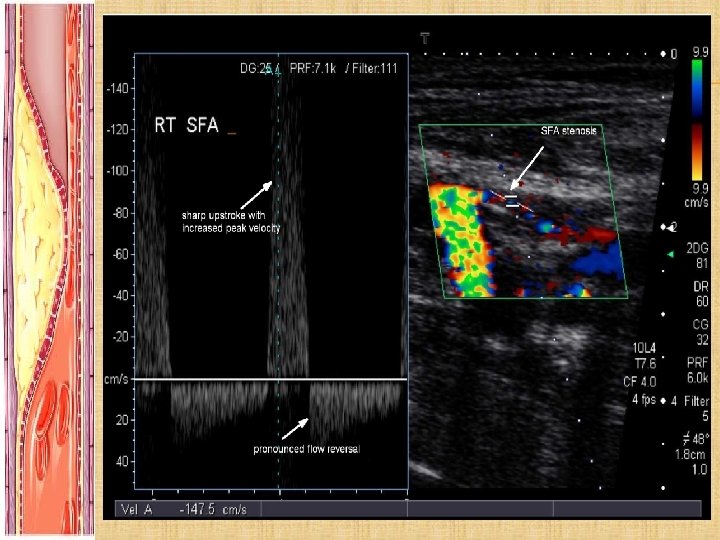

INVESTIGATIONS: BLOOD TESTS: 1. FBE/EUC/Homocysteine Levels 2. Coagulation Studies 3. Fasting Lipids and Fasting Glucose 4. HBA 1 C WHEN TO IMAGE: 1. To image = to intervene 2. Pt’s with disabling symptoms where revascularisation is considered 3. To accurately depict anatomy of stenosis and plan for PCI or Surgery 4. Sometimes in pt’s with discrepancy in hx and clinical findings NON INVASIVE: Duplex Ultrasound normal is triphasic biphasic monophasic absent